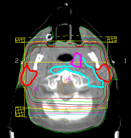

• Radiology (74)